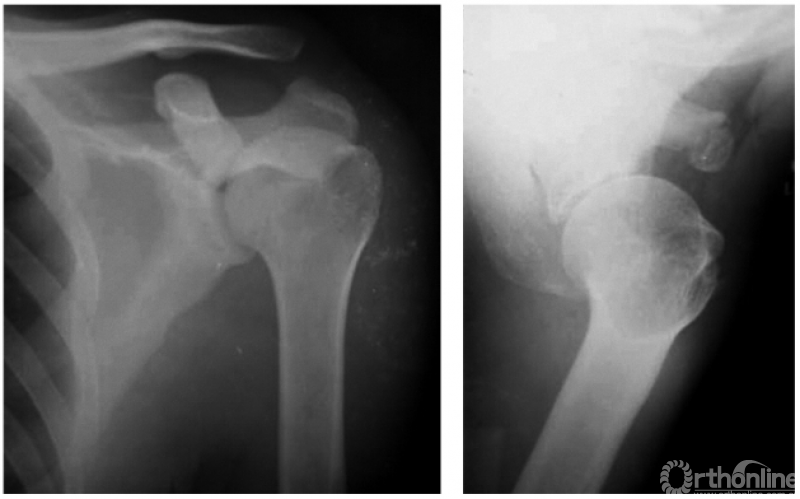

2. 肩锁关节脱位并喙锁韧带断裂

本例由于肩锁韧带及喙锁韧带均断裂致喙锁间隙扩大与肩锁关节脱位(图4)。